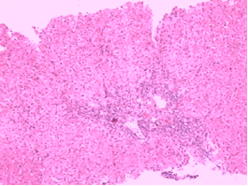

(二)過分篩選及吞噬作用脾亢時脾內單核-巨噬細胞系統過度活躍,而脾索內異常紅細胞(如球形細胞及受體、氧化劑或其它化學毒物、物理因素損傷的紅細胞等)明顯增多,並為巨噬細胞所清除,導致周圍血中紅細胞明顯減少。有些紅細胞膜上出現海因小體,或漿內有豪-膠小體,甚至瘧原蟲的滋養體;當自脾索進入血竇時,常見紅細胞因進退兩難,最後為竇壁巨噬細胞所挖除,同時紅細胞膜受到損失。反覆多次受損後,紅細胞成為球形細胞,終至無法通過基膜小孔而被吞噬。

(三)骨髓穿刺:骨髓呈造血細胞增生象,部分病例還可同時出現成熟障礙,也可能因外周血細胞大量被破壞,成熟細胞釋放過多,造成類似成熟障礙象。